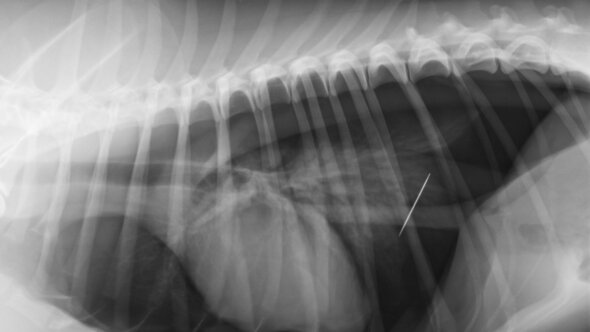

Сразу после удаления аппендикса мужчину начали мучить сильные боли, ему пришлось снова обратиться к врачам, однако они так и не могли найти причину. Паков несколько раз проходил ФГДС и делал колоноскопию, но никакого эффекта это не дало. Мужчину в итоге направили на рентген, который показал, что в его животе находится хирургическая игла. Пострадавший чебоксарец намерен обратиться в суд, чтобы добиться компенсации за моральный ущерб и траты на обследования.